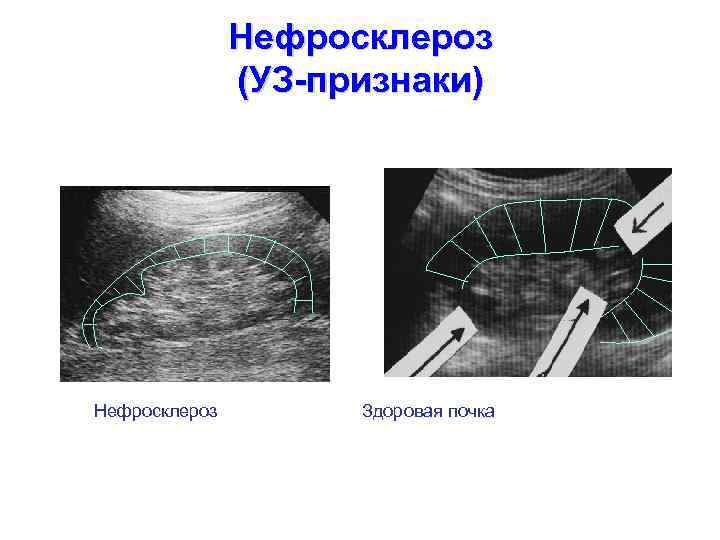

Нефросклероз (УЗ-признаки) Нефросклероз Здоровая почка

Нефросклероз (УЗ-признаки) Нефросклероз Здоровая почка

Нефросклероз (УЗ-признаки) Нефросклероз Здоровая почка

Нефросклероз (УЗ-признаки) Нефросклероз Здоровая почка